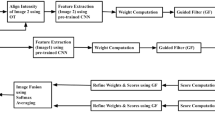

The fusion of multimodal medical images has garnered painstaking attention for clinical diagnosis and surgical planning. Although various scholars have designed numerous fusion methods, the challenges of extracting substantial features without introducing noise and non-uniform contrast hindered the overall quality of fused photos. This paper presents a multimodal medical image fusion (MMIF) using a novel deep convolutional neural network (D-CNN) along with preprocessing schemes to circumvent the mentioned issues. A non-linear average median filtering (NL-AMF) and multiscale improved top-hat (MI-TH) approach are utilized at the preprocessing stage to remove noise and improve the contrast of images. The non-linear anisotropic diffusion (NL-AD) scheme is employed to split the photos into base and detailed parts. The fusion of base parts is accomplished by a dimension reduction method to retain the energy information. In contrast, the detailed parts are fused by novel D-CNN to preserve the enriched detailed features effectively. The simulation results demonstrate that the proposed method produces better brightness contrast and more image details than existing methods by acquiring 0.7649 to 0.8986, 0.3520 to 0.4783, 0.7639 to 0.9056, 68.8932 to 81.0487 gain for quality transfer ratio from source photo to a generated photo (\(Q_{G}^{AB}\)), feature mutual information (FMI), structural similarity index (SSIM), and average pixel intensity (API) respectively.